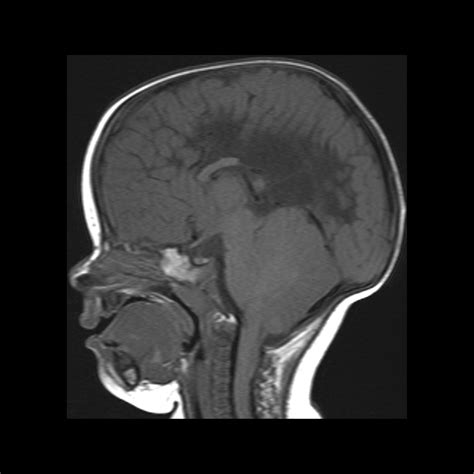

At its core, Chiari Malformation Type 2 involves a structural abnormality where brain tissue extends into the spinal canal. Because this occurs during embryonic development, it is considered a congenital condition. While Type 1 involves the cerebellum extending into the foramen magnum, Type 2 is more severe, involving both the cerebellum and parts of the brainstem. This physical displacement often obstructs the passage of cerebrospinal fluid, potentially leading to a buildup of fluid in the brain (hydrocephalus) or the spinal cord (syringomyelia).

• Magnetic Resonance Imaging (MRI): The gold standard for visualizing the brain and spinal cord, providing clear images of the extent of the herniation.

The most common procedure is a posterior fossa decompression. During this surgery, the neurosurgeon removes a small piece of bone at the back of the skull to create more space for the cerebellum. This reduces pressure on the brainstem and restores the normal flow of cerebrospinal fluid. In many cases, the dura mater (the tough membrane covering the brain) is also opened and enlarged with a patch graft to provide additional room.